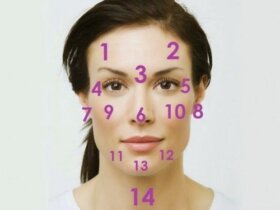

얼굴에 생기는 여러 변화가 반드시 건강 이상의 문제는 아니다. 대부분 호르몬 변화, 날씨, 약이나 음식으로 인한 변화일 수도 있지만 별다른…